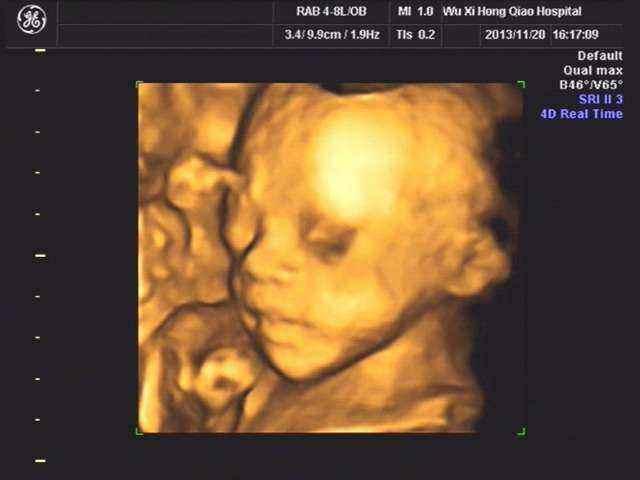

试管手术环节是费用中较为重要的一部分,包括取卵、取精、胚胎培养以及初步筛选等。而更为关键的遗传学筛查(PGS/PGD)则是对胚胎进行染色体筛查或基因检测,以确保胚胎健康无遗传病。这部分的费用根据具体治疗方法和医院而有所不同,通常在人民币3至5万元之间。